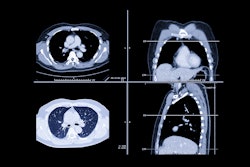

A team led by Savan Shah, MD, of Rush University Medical Center in Chicago reported that, among a cohort of 1,347 firefighters who underwent low-dose CT imaging (LDCT), only 14.6% were eligible for the test according to U.S. Preventive Services Task Force (USPSTF) recommendations -- even though some were found to have high-risk lung nodules that required intervention or surveillance.

Shah's group sought to clarify any associations between firefighters and lung cancer risk via a study that included data from 1,347 firefighters (median age, 51) recruited from the Chicago Fire Department Local 2 Union who underwent lung cancer screening between April 2022 and June 2023 as part of a pilot program established by the university. Of the study participants, 66.7% were never smokers, 25.6% were former smokers, and 7.7% were current smokers.